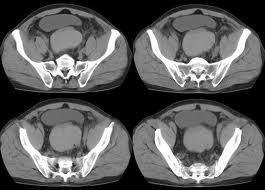

3.CT檢查

能較清楚地顯示出血血腫與其他組織的關係,當增強掃描時衰減值增加,是活動性出血的證據。